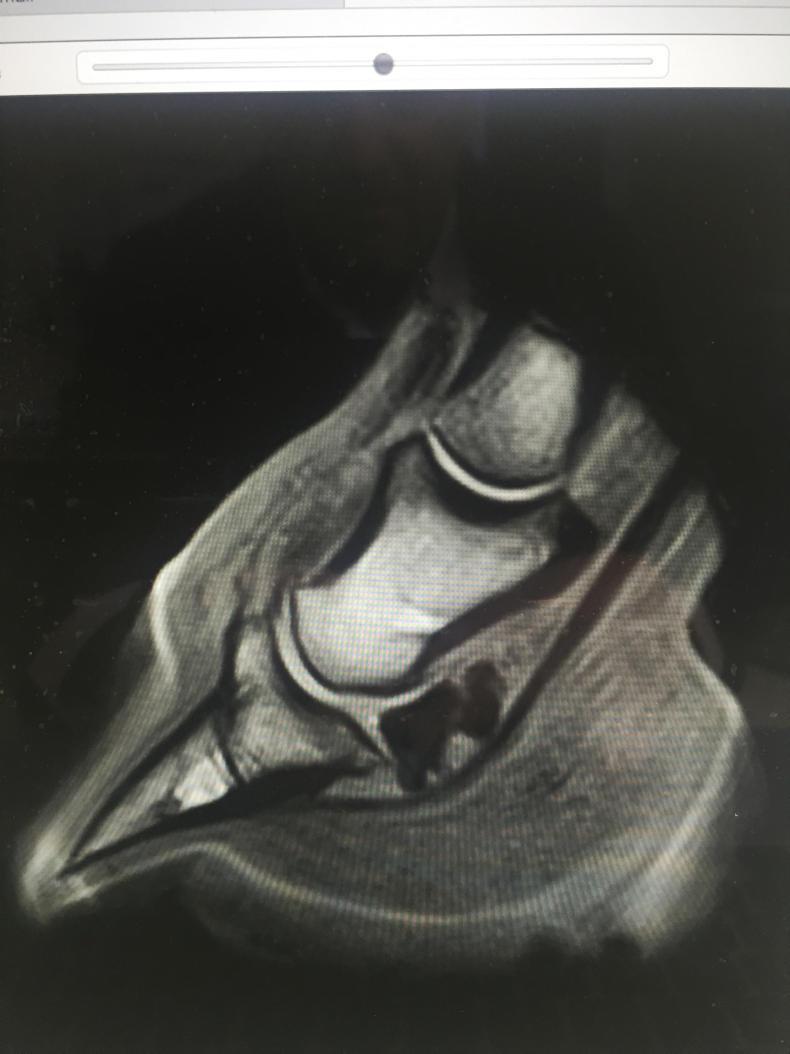

Standing equine MRI can image structures along the entire lower limb, from the foot to the knee or hock. Images are taken as slices through the limb, at an angle and position determined by the system operator according to the results of prior tests (such as nerve blocks and X-rays). By positioning images either parallel or at right angles to key structures, any clinical abnormalities such as inflammation, enlargement or degeneration are clearly revealed in a way that has no parallel in X-ray, CT, ultrasound or nuclear scintigraphy (bone scanning).